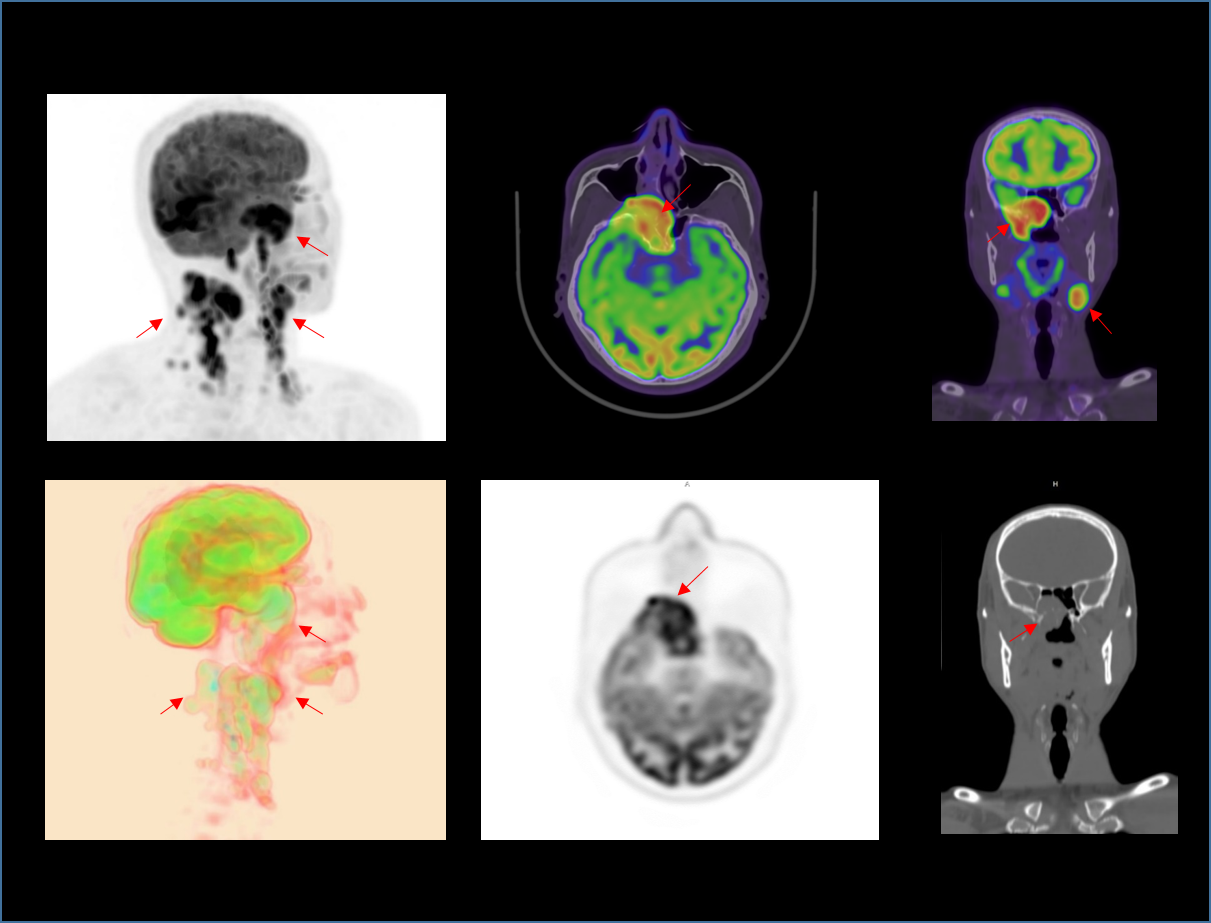

2.9mm

高いNEMA分解能。

TOF+PSF

分子イメージングの定義に革命を起こします。

600x600

画像の細部を可視化する高分解能イメージマトリクス。